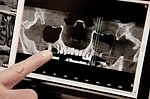

Dr. Dale Miles cautions dentists not to miss important clues revealed about the patient’s overall health on the cone beam computed tomography (CBCT) scans. Doing so can result in serious problems for the patient—and a lawsuit for the dentist.

Many dentists may be at risk for missing important changes in their patient’s scans. Dr. Miles hopes to eliminate these risks by sharing information he feels has been lacking. He said cone beam technology enables dentists to identify abnormal pathology and its causes, but he cautions dentists not to rely only on manufacturer training to learn how to recognize the changes revealed in scan data.

An experienced presenter for the dental community, Dr. Miles is excited to present information to dentists and specialists—both those who are experienced and those who are performing implant dentistry for the first time. “It’s our job to be able to recognize abnormalities within the patient’s x-ray examination and to make the appropriate referral if needed,” he said. “The right use of cone beam technology can improve the health of the patient—and the health of the dentist’s practice.”